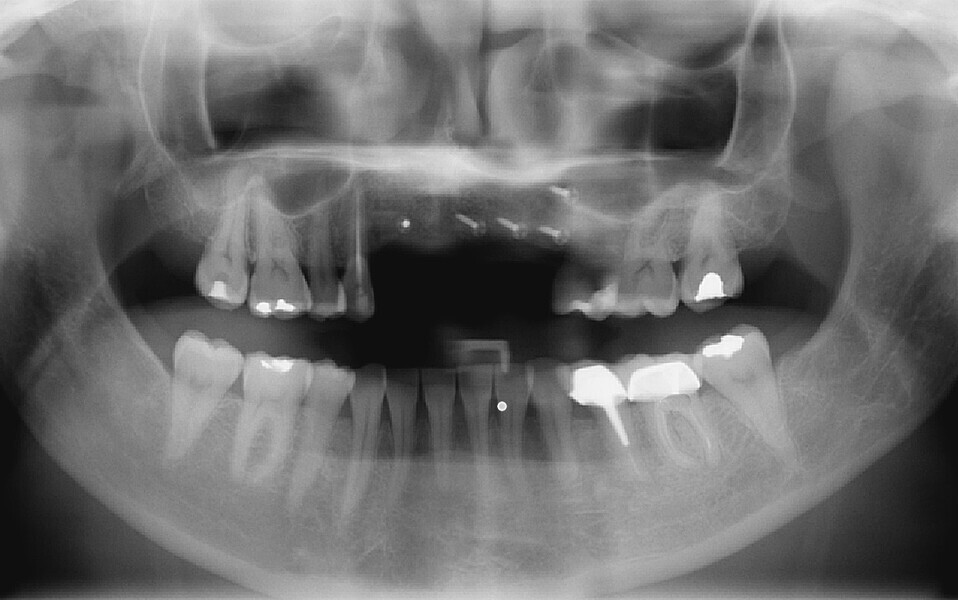

Fig. 10: Panoramic radiograph showing the grafts to be correctly healed and satisfactorily adhered to the recipient bone sites.

Fig. 40: Radiographic check-up after seven years.